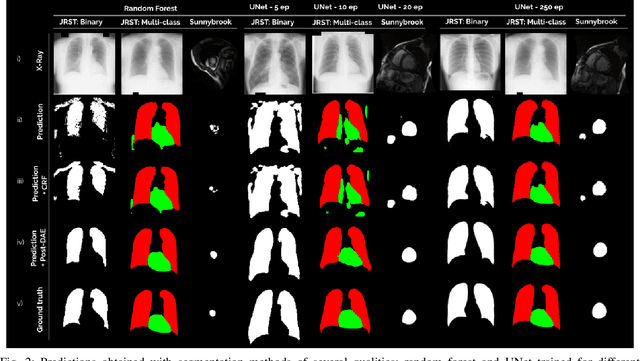

Abstract:We introduce Post-DAE, a post-processing method based on denoising autoencoders (DAE) to improve the anatomical plausibility of arbitrary biomedical image segmentation algorithms. Some of the most popular segmentation methods (e.g. based on convolutional neural networks or random forest classifiers) incorporate additional post-processing steps to ensure that the resulting masks fulfill expected connectivity constraints. These methods operate under the hypothesis that contiguous pixels with similar aspect should belong to the same class. Even if valid in general, this assumption does not consider more complex priors like topological restrictions or convexity, which cannot be easily incorporated into these methods. Post-DAE leverages the latest developments in manifold learning via denoising autoencoders. First, we learn a compact and non-linear embedding that represents the space of anatomically plausible segmentations. Then, given a segmentation mask obtained with an arbitrary method, we reconstruct its anatomically plausible version by projecting it onto the learnt manifold. The proposed method is trained using unpaired segmentation mask, what makes it independent of intensity information and image modality. We performed experiments in binary and multi-label segmentation of chest X-ray and cardiac magnetic resonance images. We show how erroneous and noisy segmentation masks can be improved using Post-DAE. With almost no additional computation cost, our method brings erroneous segmentations back to a feasible space.